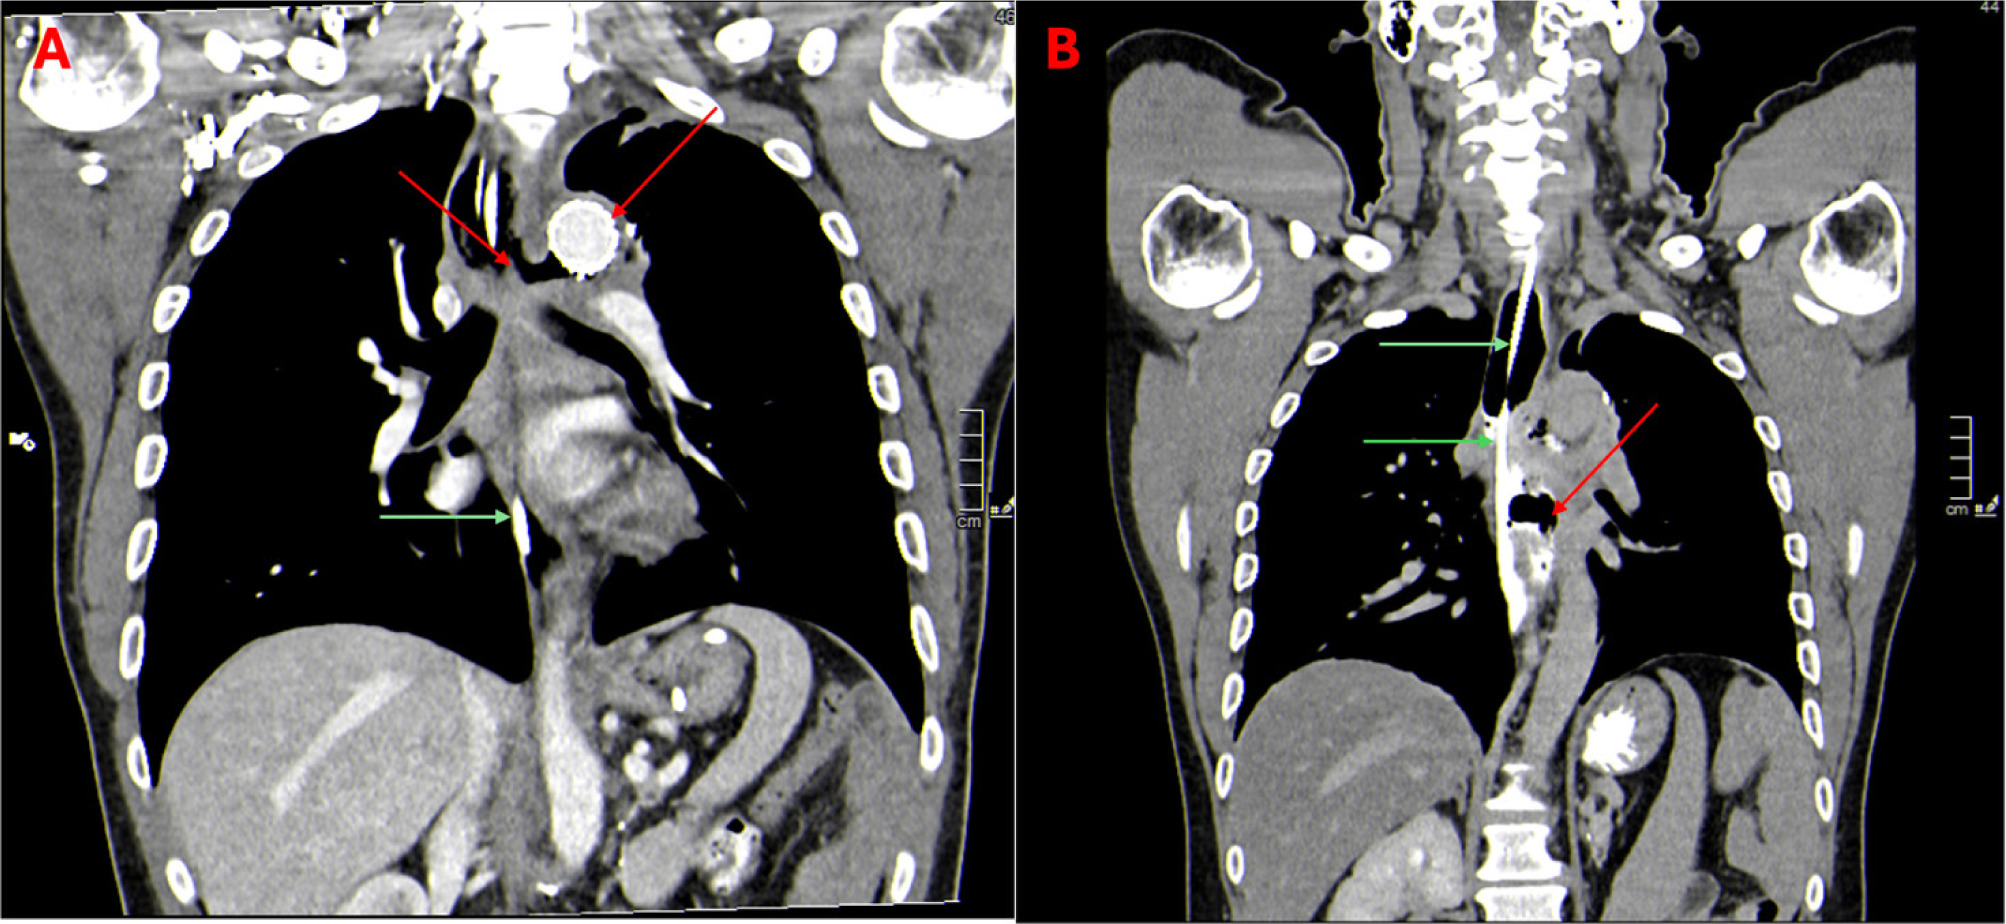

On November 11, 2024, the patient presented with hematemesis and hemorrhagic shock due to the development of a postradiation AEF, requiring ICU stabilization and endovascular aortic stent-graft implantation (Figure 1). Esophageal surgical repair was excluded, as a surgical approach was deemed infeasible. Management involved endoscopic monitoring of the esophageal fistula and broad-spectrum antibiotic and antifungal therapy for mediastinitis. Nasoesophageal and nasoduodenal tubes were used for aspiration and enteral nutrition (Figure 2). The first endoscopic approach to the esophageal fistula was the placement of a fully covered, antimigration Niti-S Beta 2 esophageal stent (20 × 80 mm) (Figures 3A and 3B).

Figure 2: (A) Aortic prothesis inserted during the acute phase of the complication (red arrow). Residual aorto-esophageal fistula is also visible, and a nasogastric tube can be seen at the esophageal level (green arrows). (B) Evidence of an esophago-mediastinal fistulous tract (red arrow). A large accumulation of iodinated contrast medium is visible within the cavity.